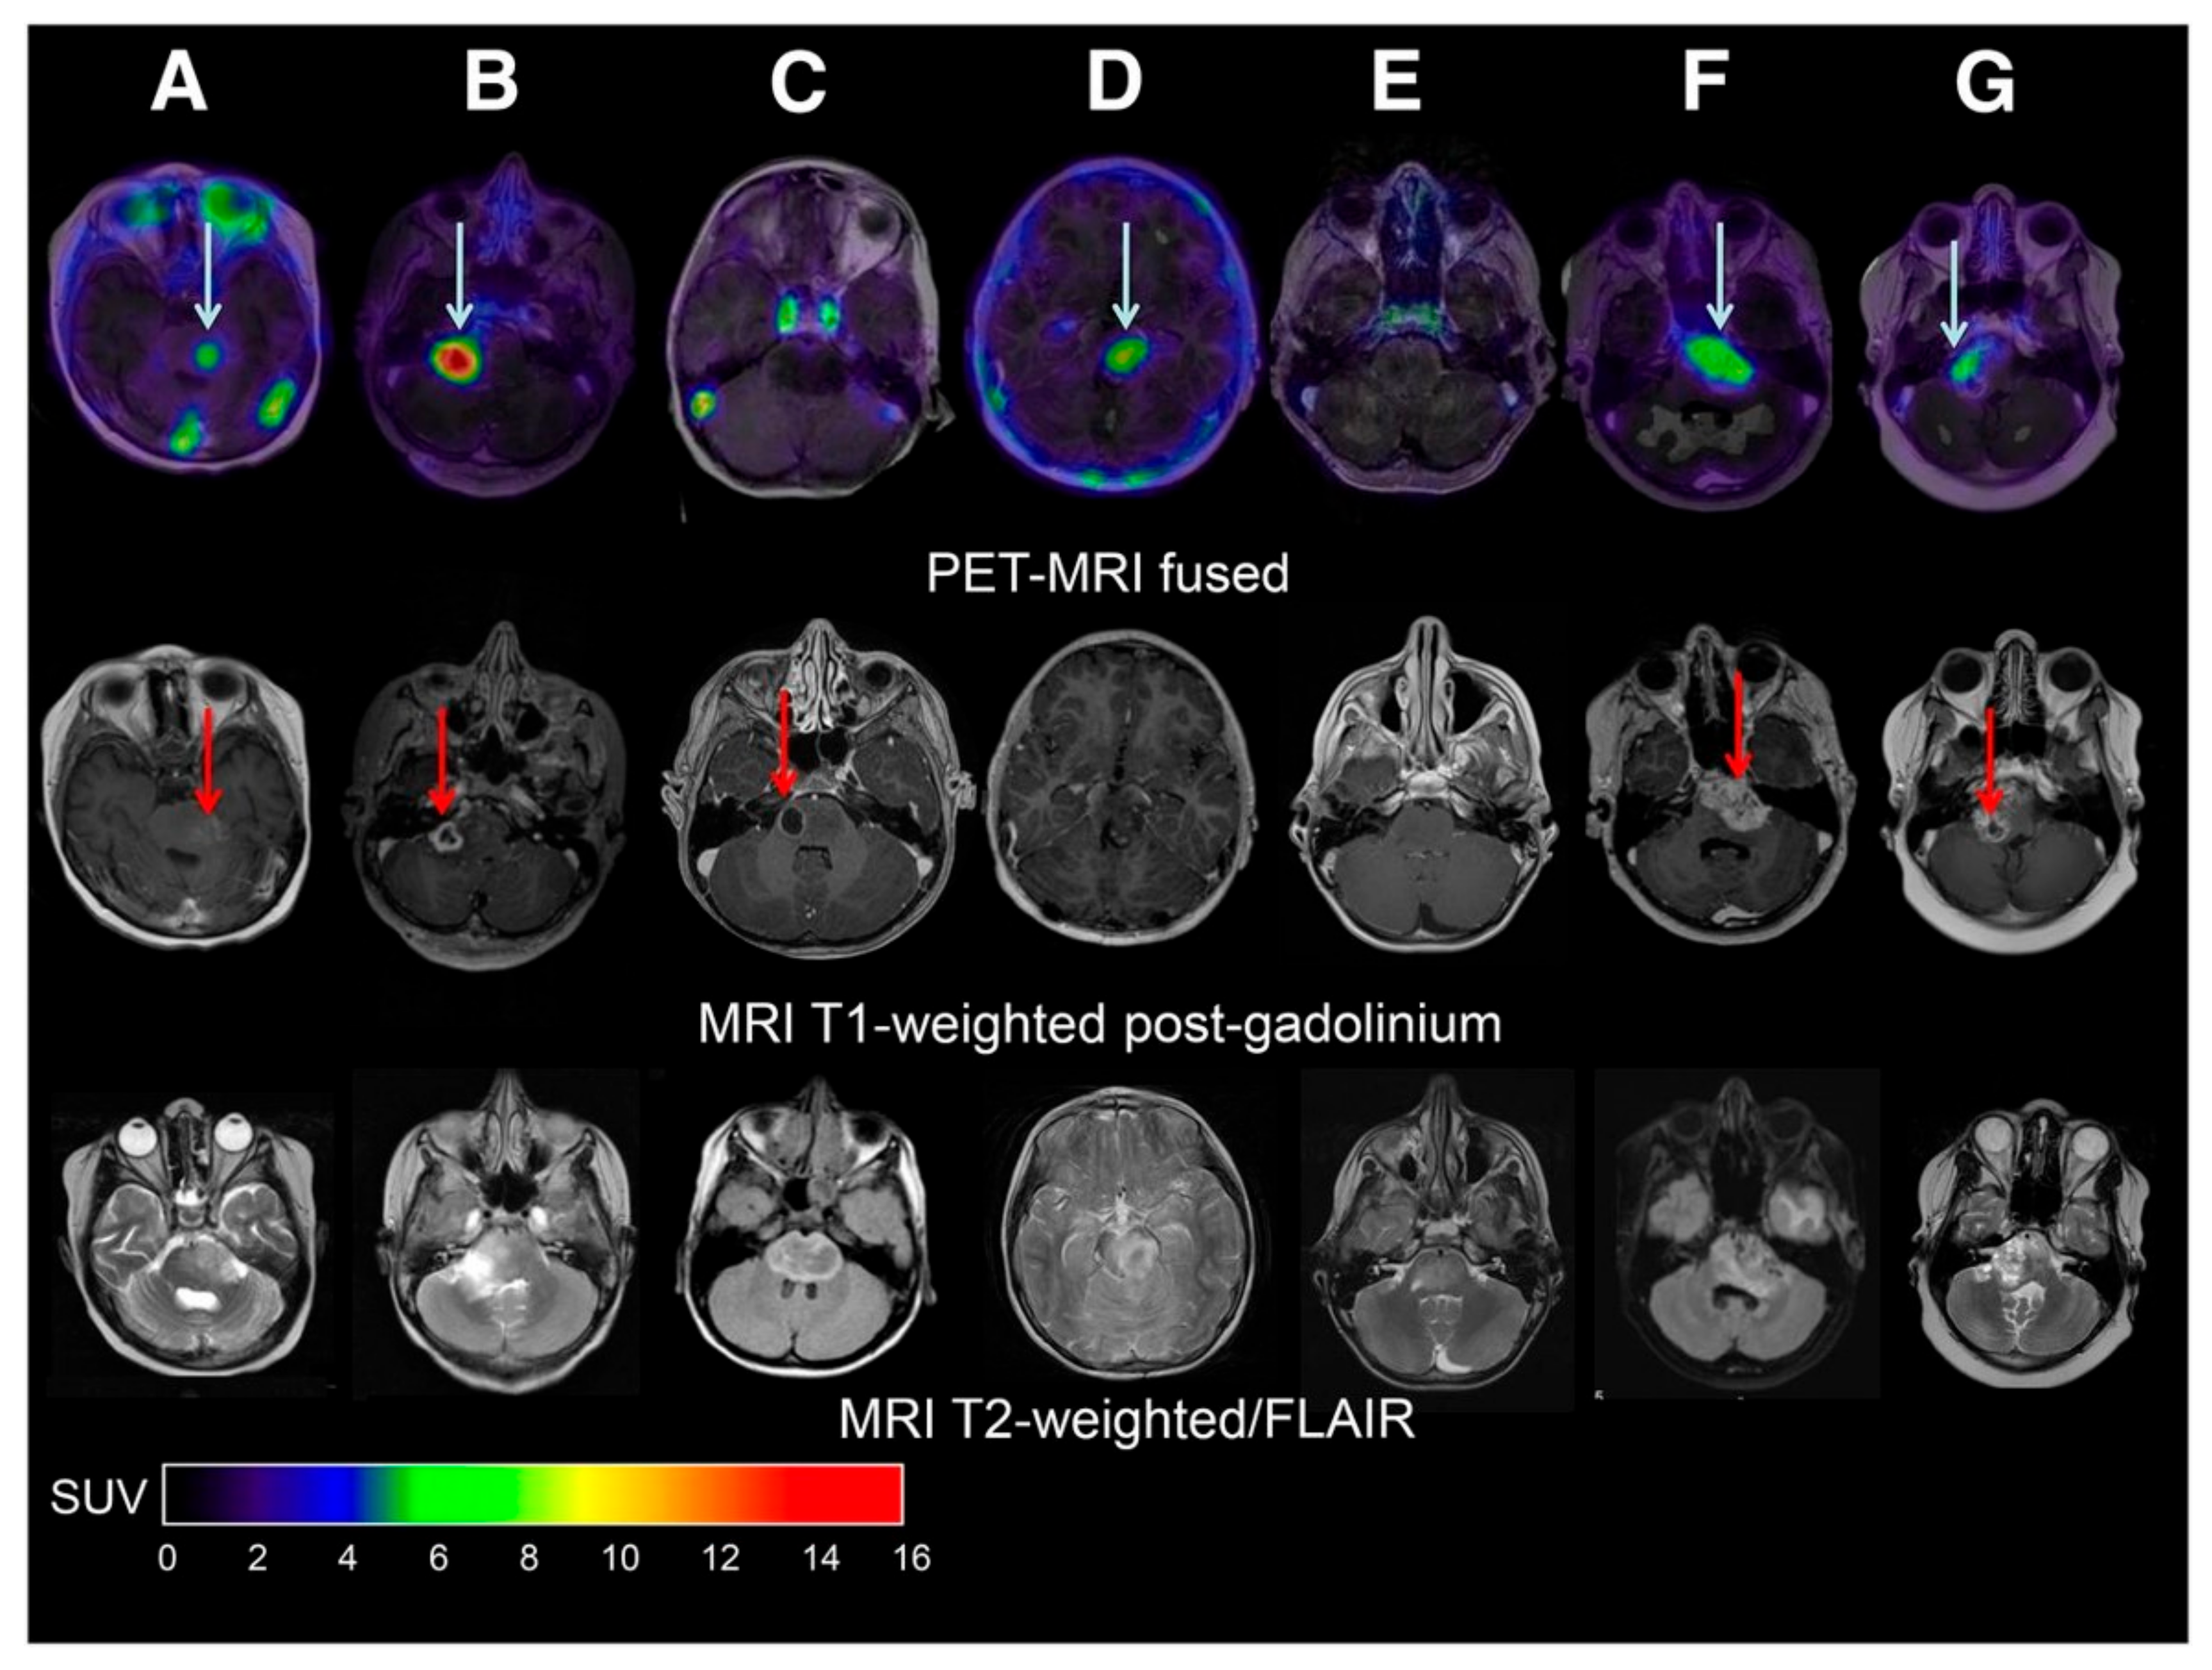

In 2010, a first study applying so-called peptide receptor radionuclide therapy (PRRT) for the treatment of CNS tumors was performed by Heute et al. [103]. The objective of PRRT is to target upregulated peptide receptors with a therapeutic radionuclide for localized therapy. As a first step, the expression and accessibility of a target peptide receptor, here the somatostatin receptor 2 (SSTR2), was studied by using an analog of somatostatin, octreotide, labeled with the positron-emitting radionuclide gallium-68 via a so-called DOTA chelator (i.e., [68Ga]Ga-DOTA-TATE, [68Ga]Ga-DOTA-TOC, or [68Ga]Ga-DOTA-NOC) [104]. When subsequent PET-imaging confirmed SSTR2 expression and accessibility by showing high uptake at the tumor site, patients were found eligible for targeted therapy using one of the DOTA peptides labeled with a therapeutic beta-particle-emitting radionuclide, either luthetium-177 or yttrium-90 [103,105,106,107]. The positron-emitting radionuclide can hereafter be used again for the assessment of therapeutic efficacy as shown in the first study using [90Y]Y-DOTA-TOC in patients with GBM, where post-therapeutic follow-up PET images showed a decreased uptake of [68Ga]Ga-DOTA-TOC, which is suggestive of therapeutic efficacy (Figure 2) [103]. Subsequent studies into PRRT for treatment of CNS tumors included patients with HGG and meningioma [105,106,107]. In meningioma, it was shown that the level of SSTR2 expression, measured by [68Ga]Ga-DOTA-TATE/-TOC uptake, correlates with the therapeutic efficacy of [177Lu]Lu-DOTA-TATE [105,106,107] or [90Y]Y-DOTA-TOC therapy [105]. In 2019, Verburg et al. performed a PET-guided drug delivery study aimed at optimizing the effect of PRRT in four patients with inoperable grade II meningioma [108]. Here, tumor uptake of [68Ga]Ga-DOTA-TATE upon intra-arterial (IA) versus intravenous (IV) administration was compared. Results showed a 2.7-fold higher tracer uptake after IA administration compared to IV administration. The potential benefit of IA PRRT for CNS tumors has further been underlined by a case report of a grade II meningioma patient treated with [177Lu]Lu-DOTA-TATE, showing a 79% decrease of tracer uptake on post-therapeutic [68Ga]Ga-DOTA-TOC images [109].

Figure 2.

Response of high-grade glioma to local therapy with a cumulated 2.2-GBq dose of [90Y]Y-DOTA-TOC given in three cycles (from left to right: study before therapy, control study 3 months after second dose, control study 3 months after third dose, and control study 23 months after third dose). (A–F) T1-weighted enhanced MR images show diminishing contrast agent in tissue surrounding resection cavity throughout therapy. (A–J) [68Ga]Ga-DOTA-TOC PET images representing somatostatin receptor status show increased tracer uptake around resection cavity before therapy (G) and normalization in control studies (A–J). Adapted from [103]. This research was originally published in JNM. Heute D, Kostron H, von Guggenberg E, Ingorokva S, Gabriel M, Dobrozemsky G, et al. Response of recurrent high-grade glioma to treatment with (90)Y-DOTATOC. J Nucl Med. 2010;51(3):397-400. © SNMMI.